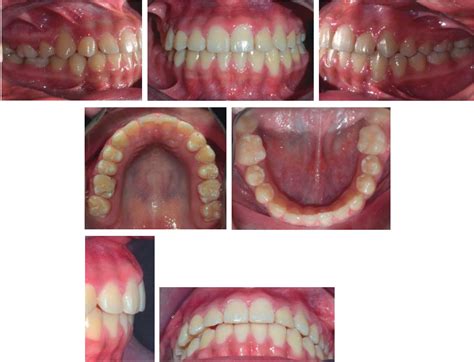

Diagnóstico: El análisis de las fotografías faciales reveló una paciente dolicofacial, cara con forma ovalada, perfil recto, nariz recta, labios competentes, sonrisa positiva, la línea media facial coincide con la línea media dental. En el examen clínico intraoral se observó: mordida abierta anterior, mordida cruzada posterior, las líneas medias superior e inferior dentales no coinciden, clase I molar izquierda y derecha, clase I canina izquierda y derecha; forma de la arcada paraboloide, ligero apiñamiento en la zona anterior superior e inferior.

Progreso del tratamiento: Se realizó la colocación de aparatología fija, brackets prescripción MBT 0.022″, bandas en primer y segundo molares maxilares, izquierdo y derecho con un botón soldado en la superficie palatina de ambas bandas y en mandíbula bandas con cajas linguales. Se colocaron arcos circunferenciales 0.016″ superior e inferior de NiTi para liberar el apiñamiento, las rotaciones y nivelar. Se aplicaron la serie de arcos indicada por la filosofía MBT hasta finalizar con arcos 0.019×0.025″ de acero.

Fueron colocados mini-implantes de la marca O.S.A.S Dewimed® auto-roscantes y auto-cortantes de diámetro de 2.5×1.6×6mm, en la zona de la línea muco-gingival por vestibular entre el primer y segundo molar, y en paladar se colocaron dos mini-implantes uno a cada lado de la sutura media palatina.5-7,10-13 Se realizó un botón acrílico con cuatro ganchos confeccionados de alambre de 0.036′ dos mesiales y dos distales a cada lado del botón, cercanos a la corona del primer y segundo molar; en el botón se hizo una ranura en la zona que está en contacto con el paladar con el fin de ser cementado con resina (Transbond XT 3M Unitek) para iniciar con la intrusión molar superior tanto en vestibular, como en paladar simultáneamente y para obtener un vector de fuerza vertical, además de insertar el tornillo con cierta inclinación para aumentar la superficie cortical de anclaje7,10 de acuerdo con el modelo sugerido por Ludwig9 (Figuras 5 y 6). El botón palatino se mantuvo en la boca durante 8 meses.

Resultados: Los resultados fueron obtenidos con el análisis y comparación de las fotografías modelos y cefalometrías de inicio y finalización del tratamiento. La fotografía facial de sonrisa mostró una mejora estética importante, se corrigió la desviación de la línea media y el apiñamiento dental, no se observó una diferencia en cuanto a la exposición dental comparada con la fotografía inicial, el perfil se mantuvo como al inicio de tratamiento.

Al realizarse la comparación de las fotografías iniciales y finales se la alineación y nivelación de las arcadas superior e inferior, el cierre de la mordida abierta anterior que dio como resultado una sobremordida vertical de 3mm y una sobremordida horizontal 4mm, también la consolidación de la clase I molar y canina, mordida cruzada de los segundos molares superiores.